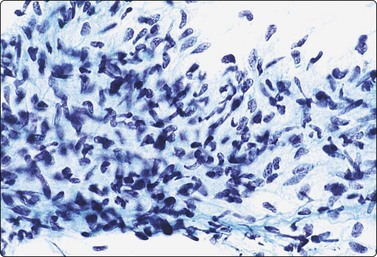

Most malignant peripheral nerve sheath tumors (MPNST) show the pattern of spindle cell sarcomas; some are highly pleomorphic and some have epithelioid features (Fig. 15.50A). Cells from a low-grade tumor may be only moderately pleomorphic. In high-grade tumors, the smears are highly cellular and the cells have elongated, spindly, atypical nuclei (Fig. 15.50B). Mitotic figures are not uncommon. Pleomorphic MPNST often displays a cytomorphology resembling that of a pleomorphic sarcoma of MFH type, including multinucleated tumor cells with bizarre nuclei. Nuclear chromatin is coarse and irregular. Cells are single and in clusters with intercellular collagen, and a background of myxoid material is occasionally present. Neurofibrosarcoma in von Recklinghausen’s disease may be difficult to diagnose as these tumors may show a mixture of benign and malignant areas (Fig. 15.51). The variable cytologic features of MPNST in FNB smears have been recorded in a number of series.63,64 Positivity for S-100 protein, an important feature in benign neurogenic tumors, is of less diagnostic value in MPNST, as many tumors are negative and positivity often focal.

image image

Fig. 15.50 Malignant peripheral nerve sheath tumor (MPNST)

(A) Some of MPNST are highly pleomorphic and some have epithelioid features (MGG, HP); (B) In high-grade tumors, the smears are highly cellular and the cells have elongated, spindly, atypical nuclei (H&E, HP).